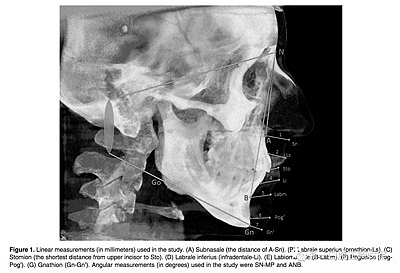

所有患者拍攝頭顱CBCT,要求以最大的牙尖交錯位, 放松嘴唇位置, 不能移動他們的頭部或舌頭。CBCT圖像被轉(zhuǎn)化為數(shù)字成像, 然后使用 Simplant Pro 軟件測量軟組織厚度 和角度的測量,測量指標見Figure 1。所有厚度測量都是隨機盲法下由經(jīng)驗豐富的不知道病人生長型的口腔放射科醫(yī)生測量。頭影測量是由牙醫(yī)測量。